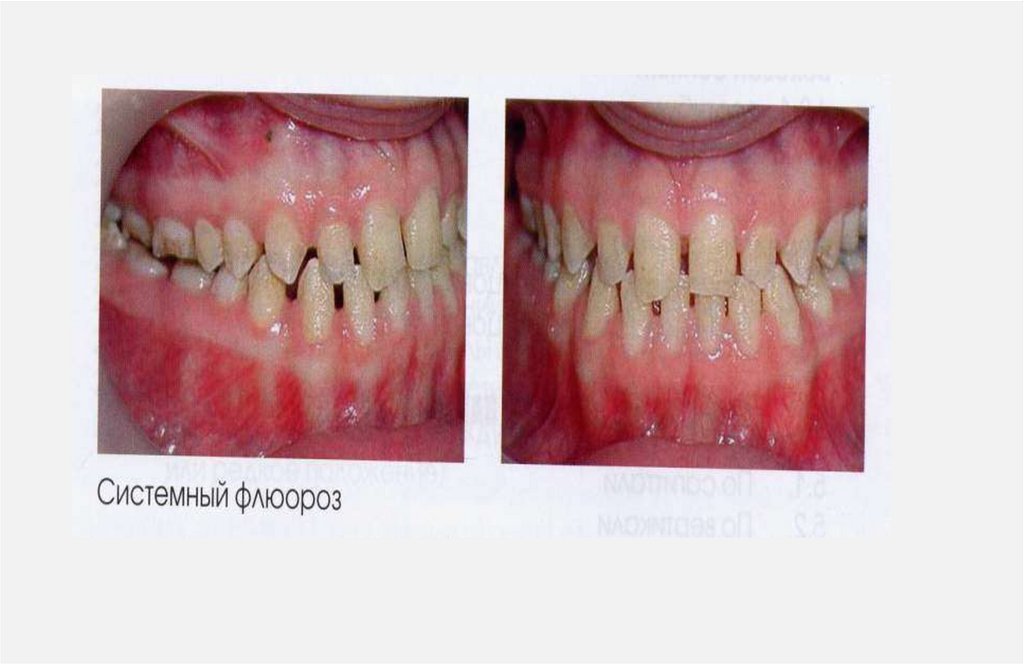

1. АНОМАЛИИ ЗУБОВ

1.1. Аномалии формы зуба

1.2. Аномалии структуры твердых тканей зуба

1.3. Аномалии цвета зуба

1.4. Аномалии размера зуба (высоты, ширины, толщины) (1.4.1. макродентия, 1.4.2.

микродентия)

1.5.Аномалии количества зубов ( 1.5.1. Гиперодонтия, 1.5.2. Гиподонтия)